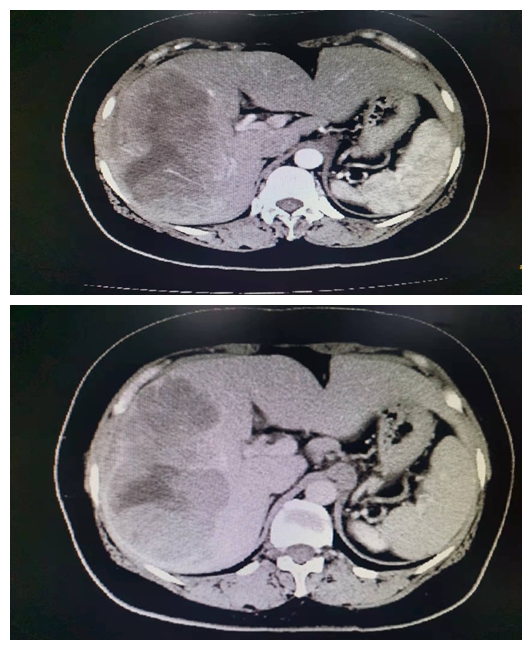

2021年11月17日,我院肝胆胰脾外科收治了一位右上腹疼痛5天的患者,患者告知其于4年前做过左侧肾上腺皮质癌手术、子宫肌瘤手术手术及乙肝病史,通过完善CT及其他相关检查后,发现患者肝右叶肿瘤性病变,肿瘤几乎长满了右半肝,直径达到12cm,结合其他检验数据诊断为:肝右叶巨块型肝癌。

入院后肝胆胰脾外科主任余建中积极组织川北医学院对口支援教授钟杨、副主任医师胡晓华及科室质控组对患者进行了全面的术前评估讨论,通过CT三维重建,仔细测量肿瘤的体积大小和与周围胆管、门静脉、肝动静脉的关系,发现肿瘤贴近下腔静脉等大血管,但未发现癌栓,其他部位无转移性病灶;左半肝已代偿性增大,约占整个肝脏体积的50%左右;患者肝功能A级,如果行右半肝切除术,可达到肿瘤根治的目的。但因为肝脏结构复杂,切面易出血,而且切除范围多局限于左肝外侧叶和肝第Ⅳ、Ⅴ、Ⅵ段的病灶。而右半肝占肝脏总体积的55%左右,行右半肝切除术难度更高、风险更大,对技术水平要求十分高,只有具备成熟的肝切除技术才能顺利完成。